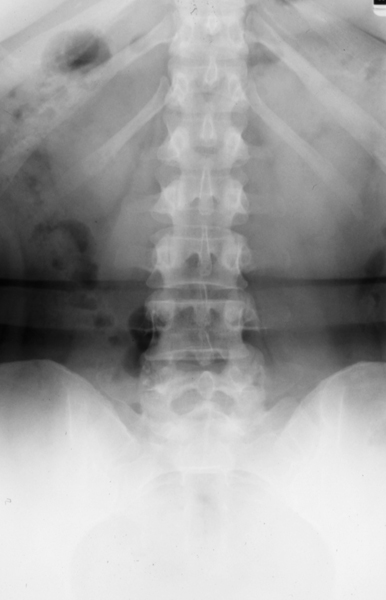

Radiology MS 185 - Normal Lumbar Spine

Identify: Frontal - vertebral body, pedicle, lamina, spinous process, transverse process, intervertebral disc